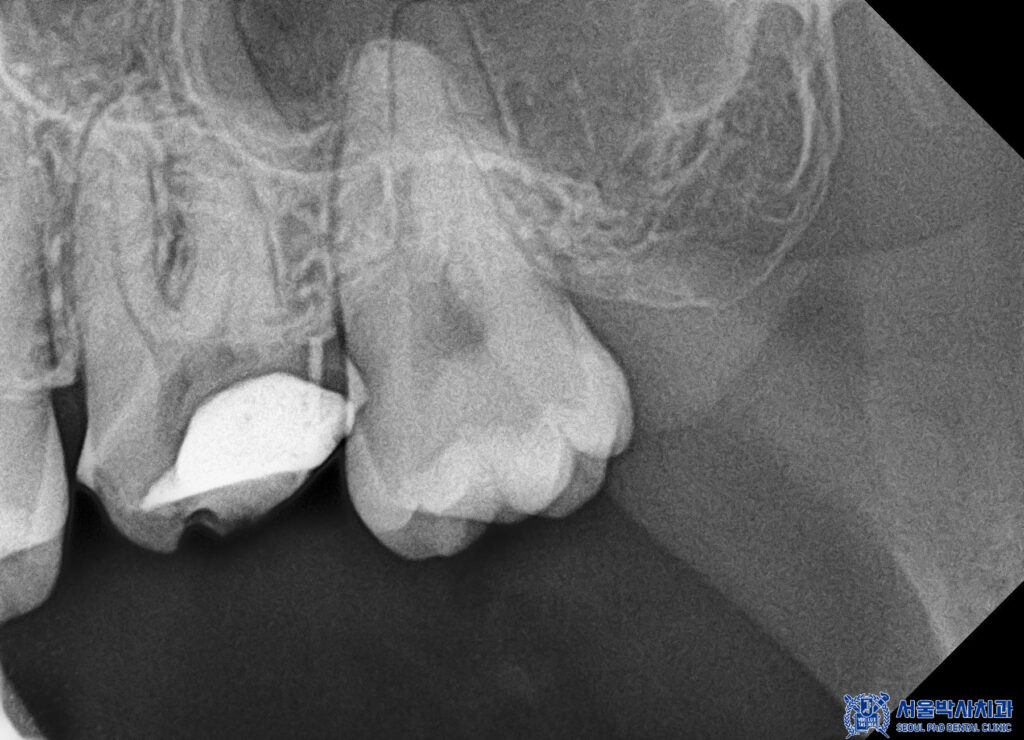

파노라마를 촬영하여 확인해 보니,

뿌리 쪽에 염증이 있는 것을

볼 수 있었는데요.

방사선 사진상 치아 뿌리 끝 주변으로

뼈가 손상된 소견이 확인되었습니다.

이는 치아 내부 신경에 염증이 생기면서

뿌리 끝까지 번진 상태로,

추가적인 치료가 필요한 상황이었습니다.